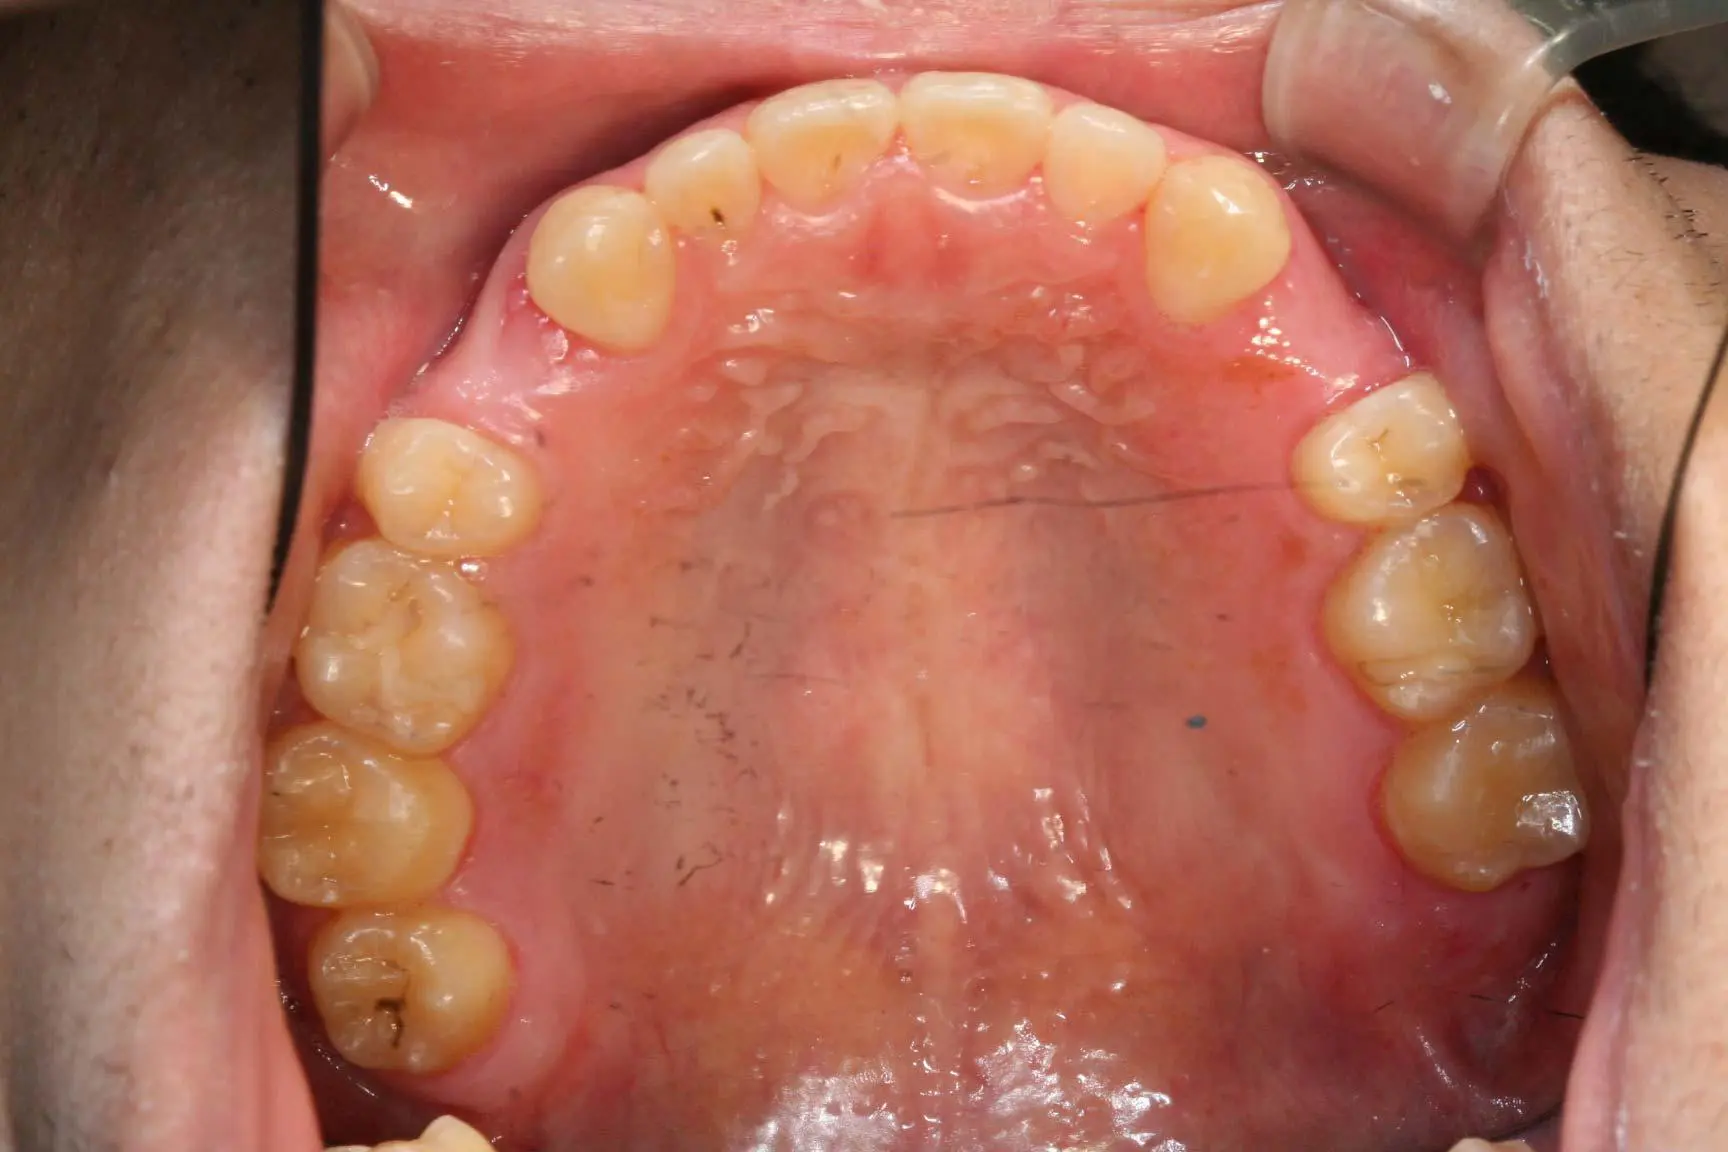

矯正+サイナスリフト ブロック骨移植

年齢 32歳 性別 女性

治療期間 3年 費用 2,600,000円

矯正+サイナスリフト ブロック骨移植 矯正+サイナスリフト ブロック骨移植